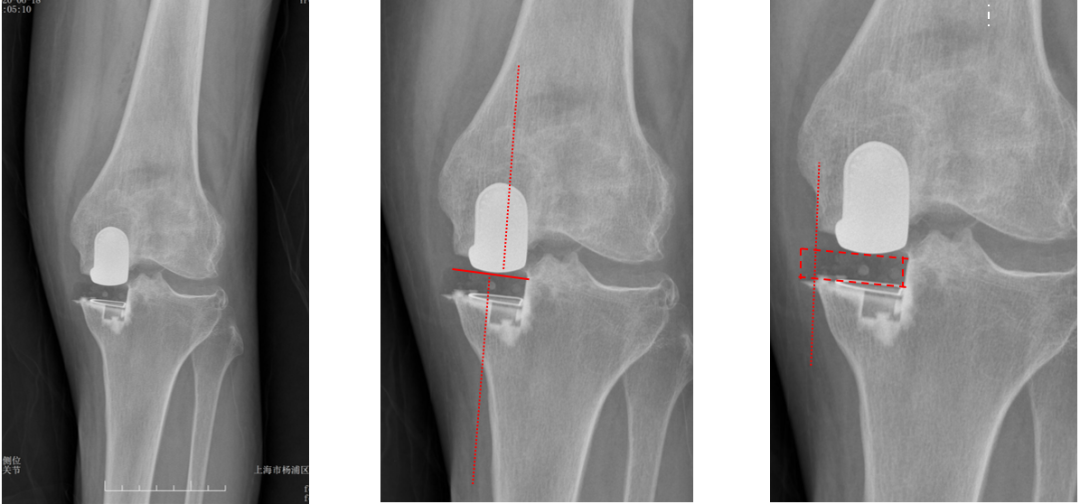

假体位置分析

正位片标准胫骨和股骨假体位置

AP位假体位置:胫骨假体轻度外翻,外侧缘与胫骨平台外侧缘齐平; 股骨假体长轴与胫骨假体垂直,与胫骨假体中线一致。

侧位片标准胫骨和股骨假体位置

侧位片假体位置:股骨假体后倾38°,假体后缘与股骨后髁齐平,胫骨假体后倾3°,与胫骨平台前后缘齐平。

标准胫骨和股骨假体位置

胫骨假体厚度合适

胫骨垫片厚度合适:术前外翻畸形基本矫正,残留2-3°外翻

胫骨假体后倾角度大

侧位片胫骨假体位置:胫骨假体后倾15°,前后缘齐平。

股骨假体偏小

侧位片股骨假体位置:股骨假体偏小,与胫骨假体后缘不齐平;屈曲35°,未包容股骨后髁。

股骨假体偏内放置

AP位胫骨与股骨假体位置:股骨假体中轴线与胫骨假体中线不一致,偏内侧,且外翻。

股骨假体偏外放置

AP位胫骨与股骨假体位置:股骨假体中轴线与胫骨假体中线不一致,偏外侧,且内翻

矫正不足、矫枉过正